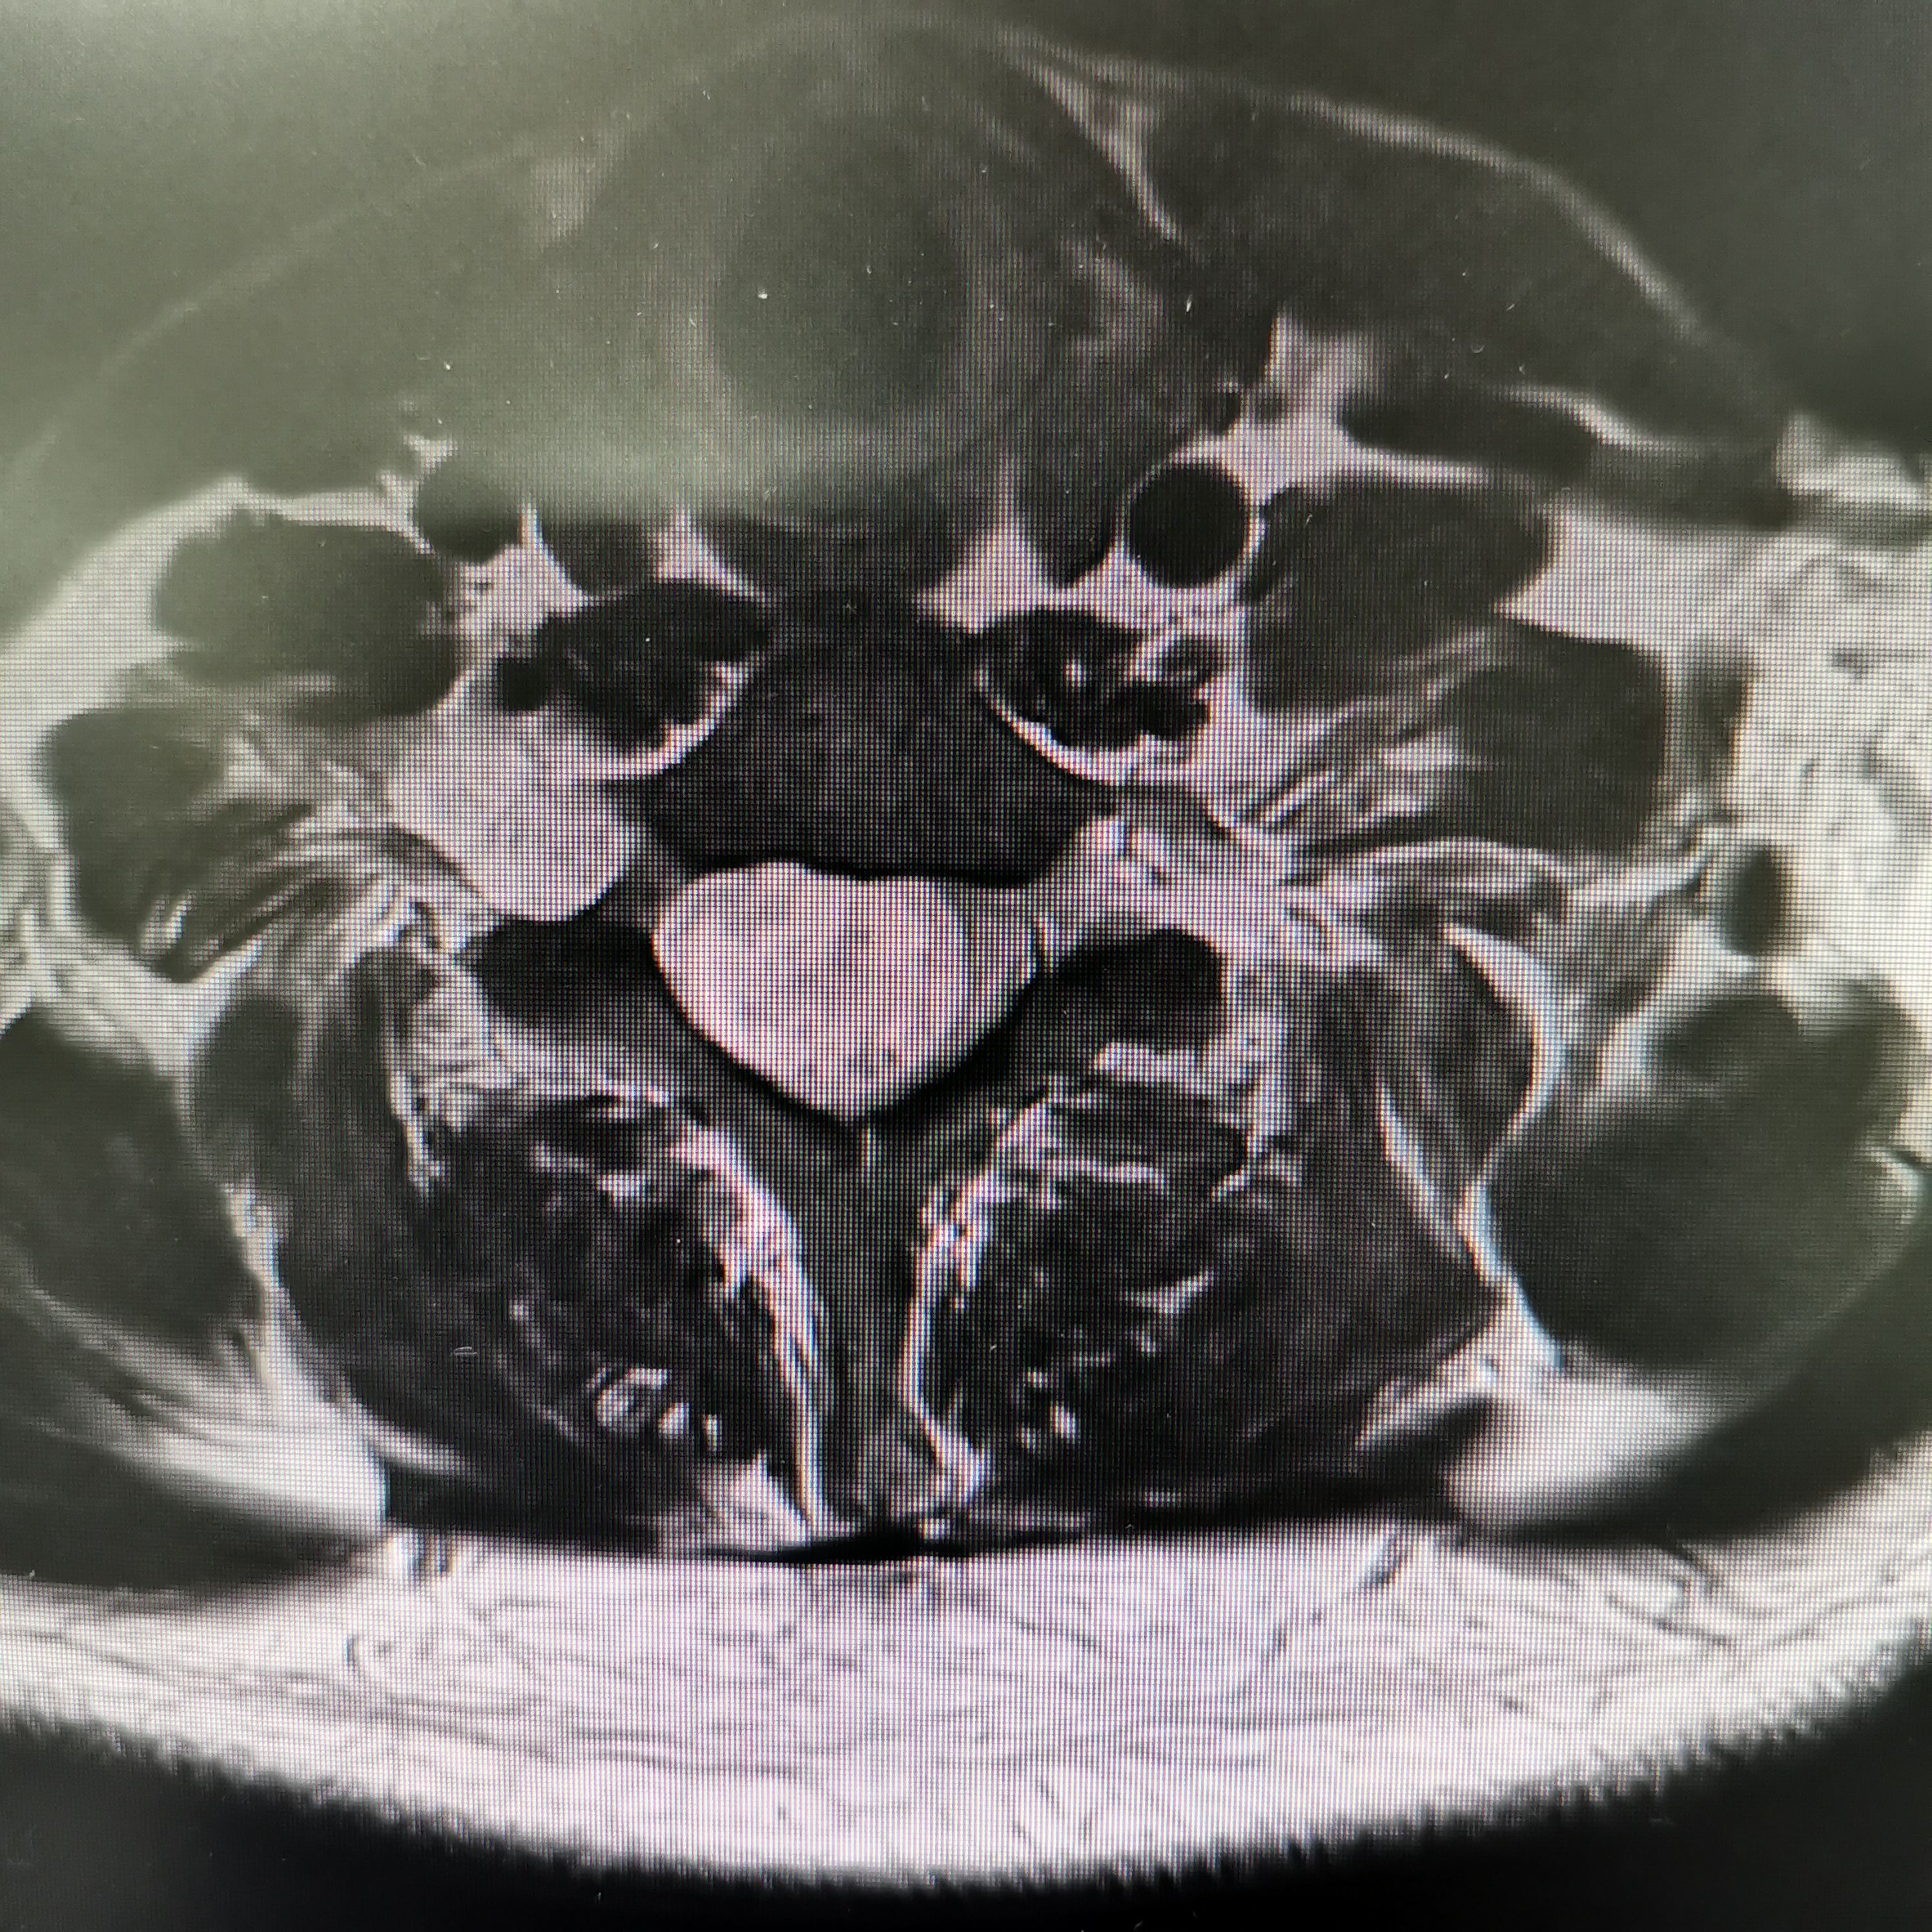

脊髓脊柱-脊髓脊柱肿瘤

神经纤维瘤病的治疗需要综合考虑患者的病情、症状、年龄、身体状况等因素,制定个性化的治疗方案。